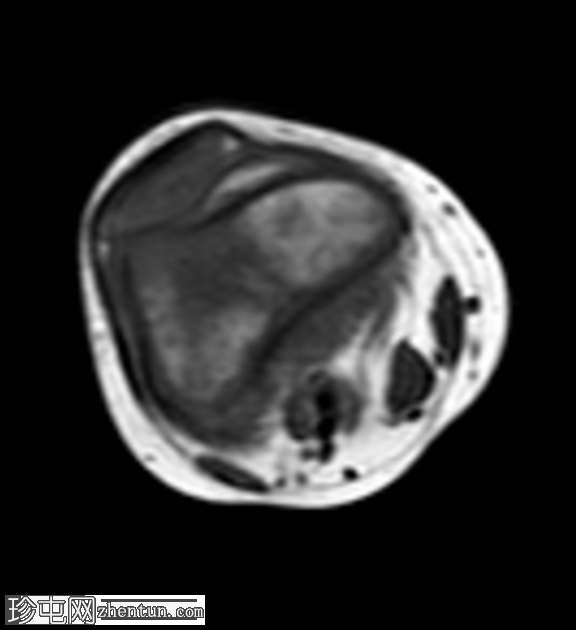

6.png

轴位

T1加权像

增强扫描显示病灶环强化,周围骨髓强化,骨骺和干骺端亦强化。

注射造影剂后,脓肿壁及周围炎症性骨髓水肿出现特征性的环状强化,从而确诊为这种特定类型的亚急性骨髓炎。